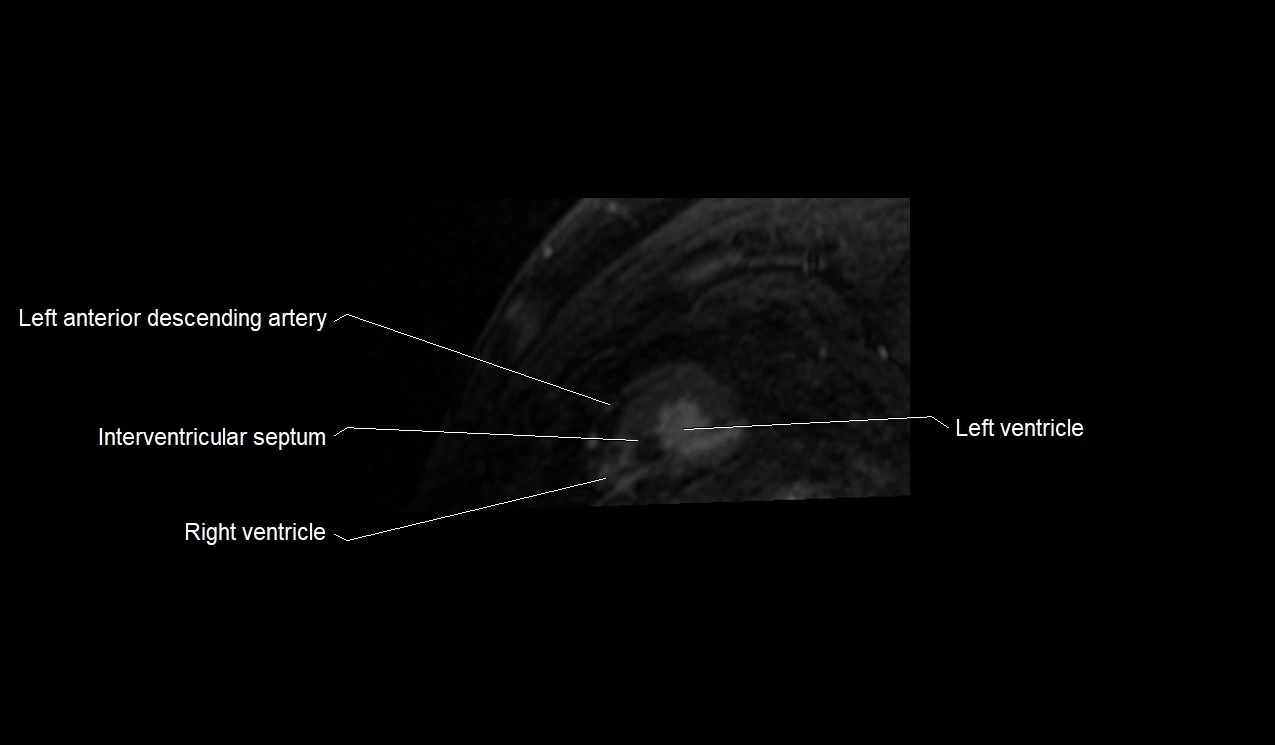

- Left anterior descending artery (LAD)

- Interventricular Septum

- Left ventricle

- Right ventricle